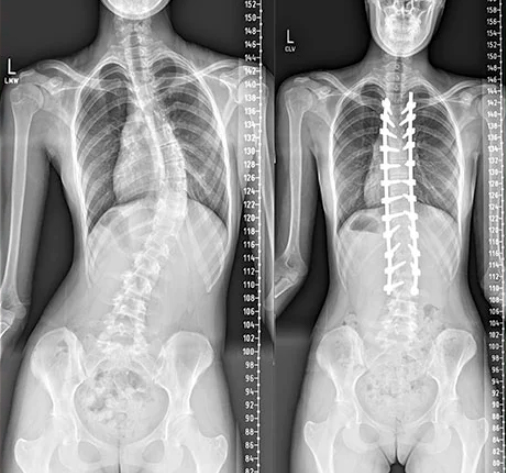

Correção de escoliose “C” idiopática toracolombar